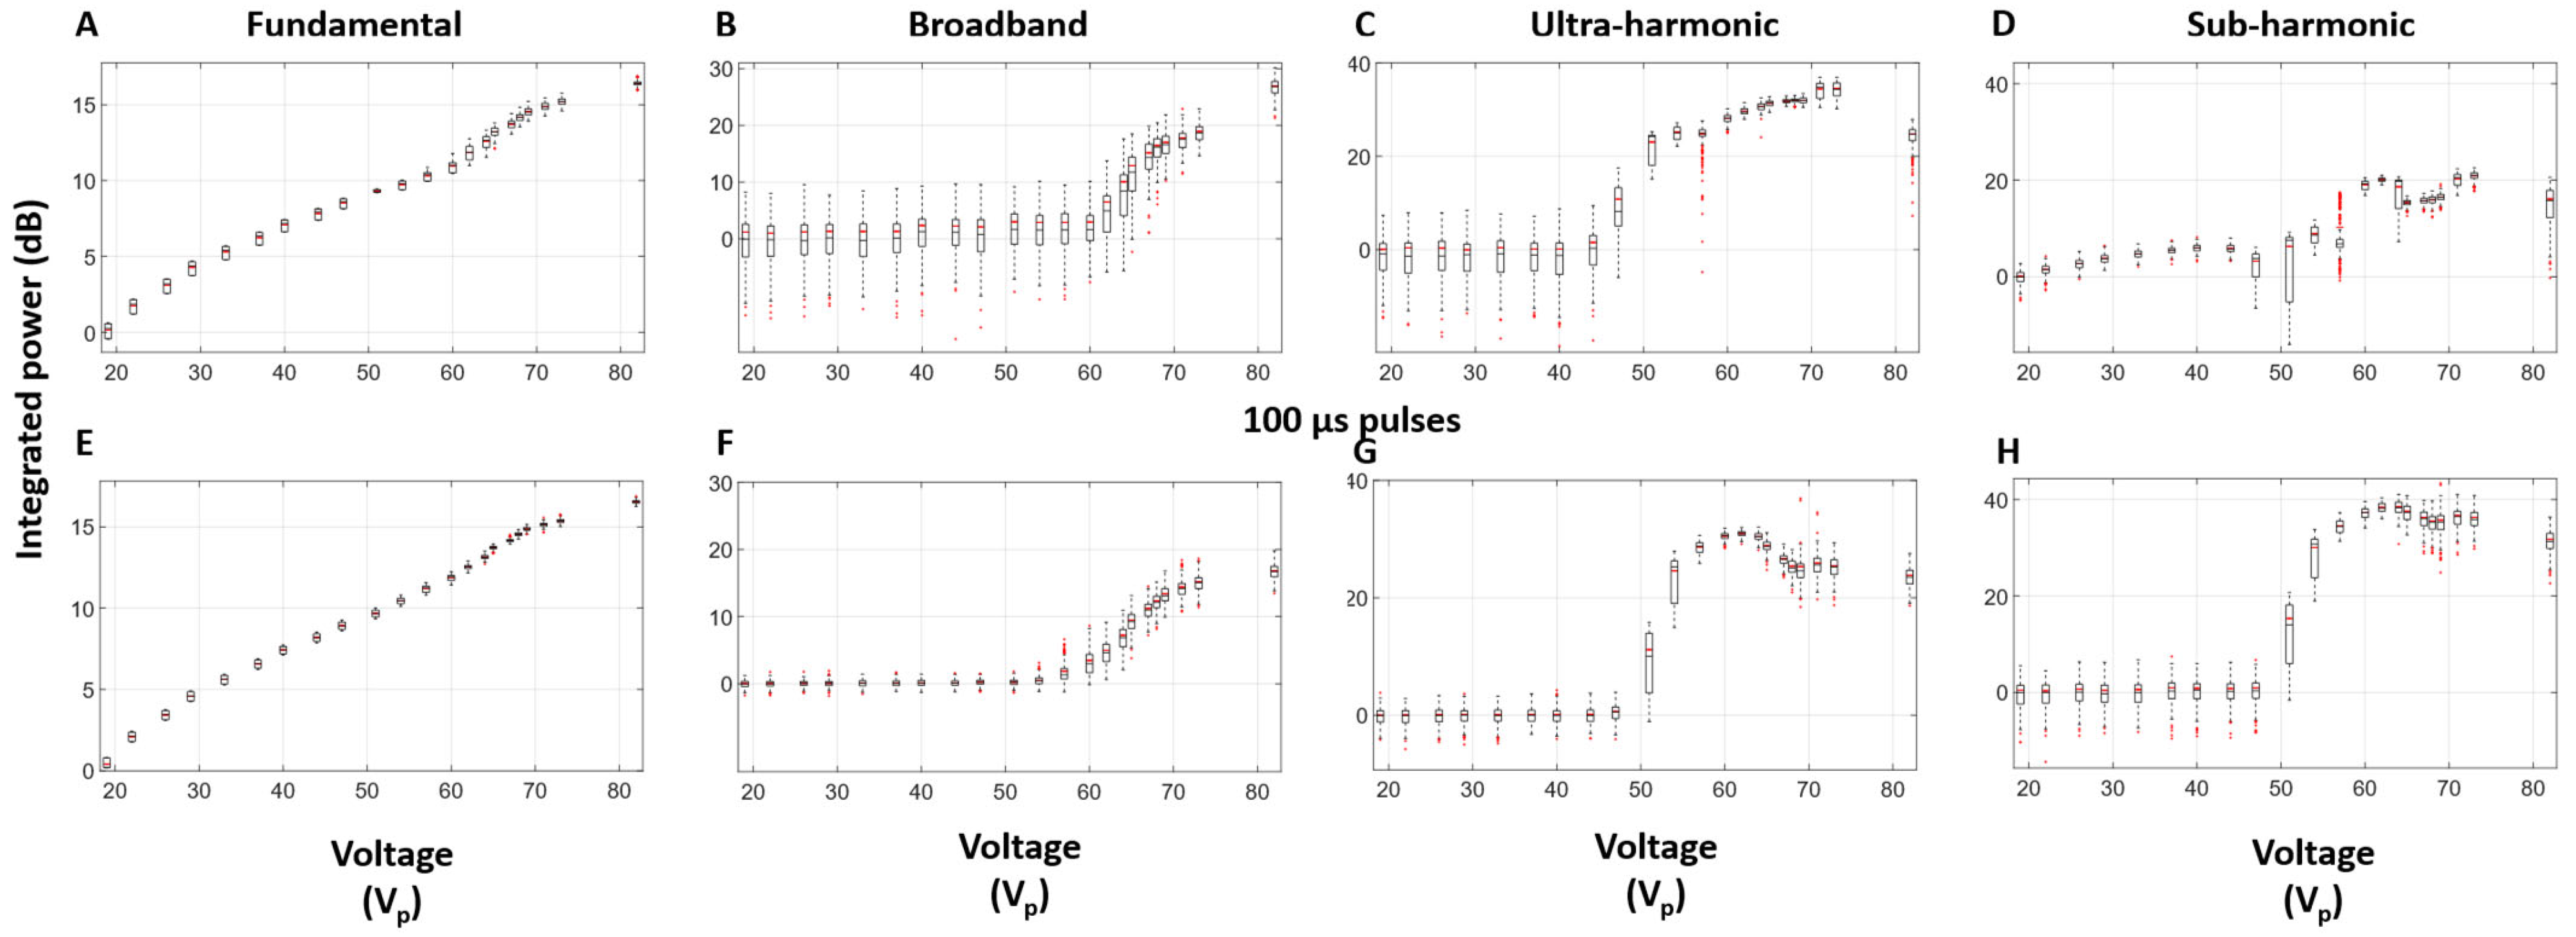

3.3. Self-Sensing Signals in Water-Filled Lumens

3.4. Self-Sensing Signals During Clot Treatments